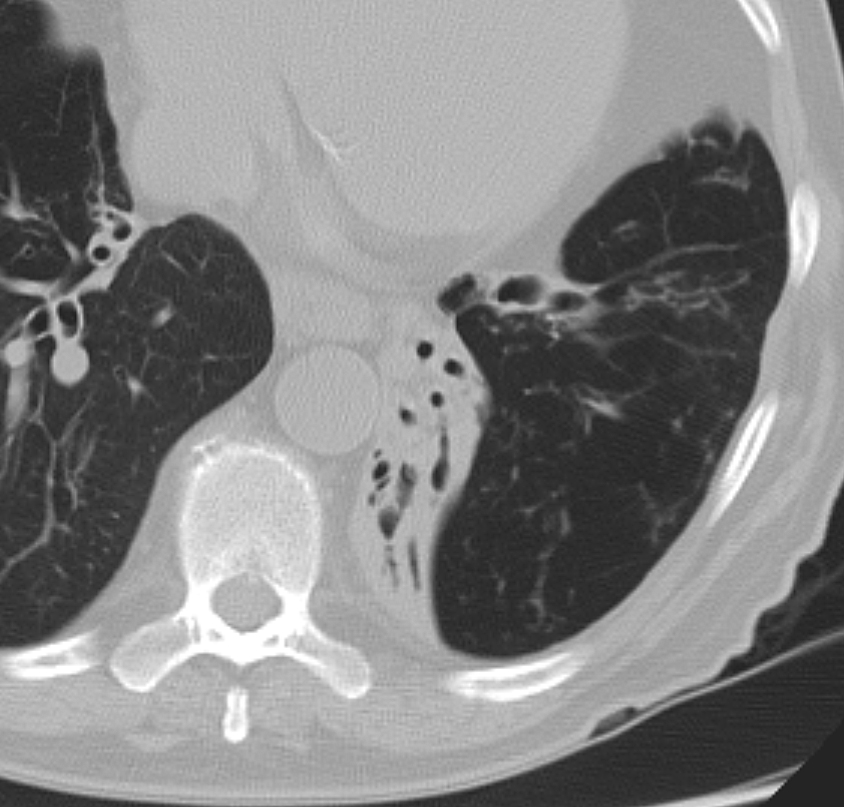

LLL collapse Case 11 axial CT